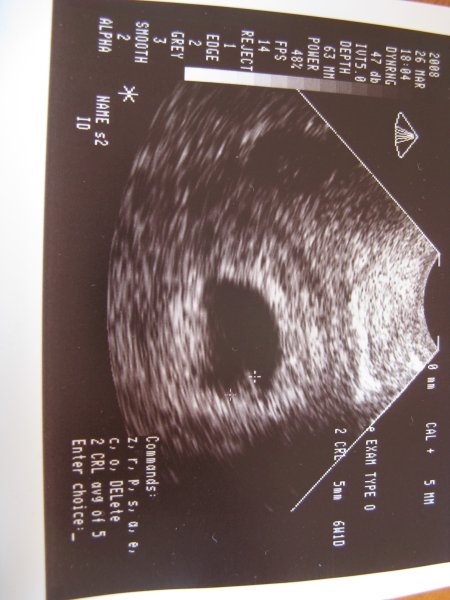

És hát így kora reggelre van egy kis meglepetésem. Nem tudtam aludni, mert olyan éhes voltam :wink:

Kép

Gondolhatjátok, h nagyon meglepett minket és nagyon boldogok vagyunk!

Mennyi idős vagy? Mert a képen én sok mindent nem látok, a pacán kívül, gondolom, akkor ez még nagyon az eleje.

én 6hetes 1 naposnak látom. Jobb sarokban: 6W1D! :lol:

Köszi a gratulációkat! Persze még azért majd a 12 hét után fogok teljesen feloldódni.

Ja amúgy 5mm és volt szívhang is.

A UH szerint 6+1 de a doki ugyanazt a szülési időpontot számította, mint a kalkulátor nov. 16.

Ezért a vonalzó 6+4 re írja.

Péntek 13.-a óta :lol: csak nem mertem mondani amíg doki nem látott, mert én sem hittem el.